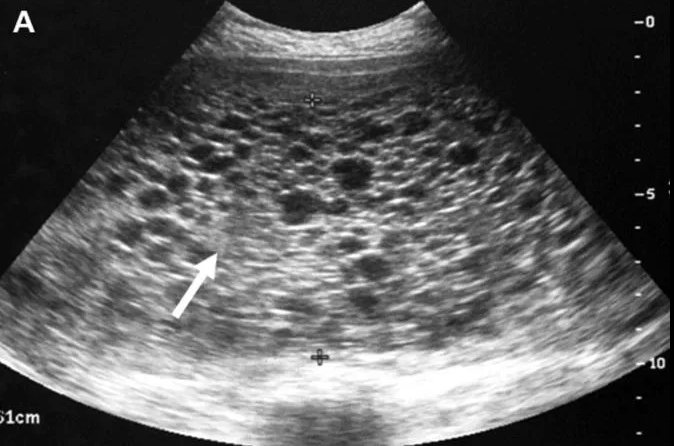

The name of this abdominal US finding.

What is intussussception?